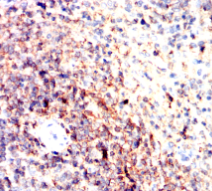

IHC    1/100 - 1/500